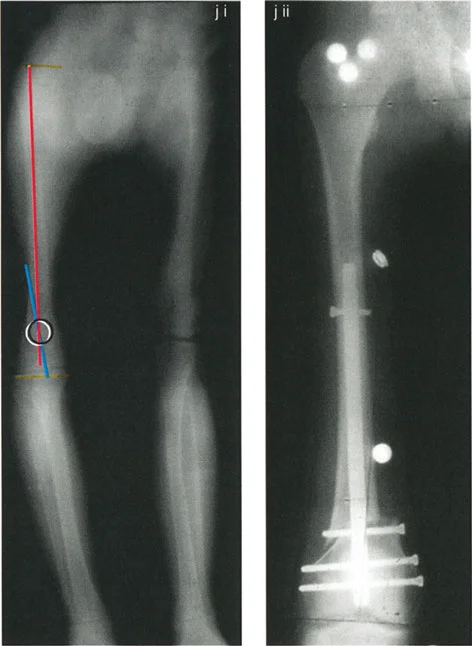

أمثلة سريرية لإعادة محاذاة الفخذ البعيد

1. بضع العظم المستعرض المطيل (قاعدة 1):

طفلة تبلغ من العمر 8 سنوات تعاني من تشوه وحشي قريب من المفصل ناتج عن توقف نمو ما بعد الصدمة. يتم رسم المحور الميكانيكي البعيد (DMA) بزاوية 87 درجة من مركز الركبة. يتم رسم المحور الميكانيكي القريب (PMA) باستخدام فرق زاوية 7 درجات (AMA). يقع التقاطع (CORA) عند صفيحة النمو، بقياس 30 درجة. يسمح الإطالة عبر صفيحة النمو مع استئصال قضيب عظمي مركزي وحشي بإعادة محاذاة مثالية. محور تصحيح الانحراف هو الحلقة الغضروفية المحيطة إنسيًا. نظرًا لأن مركز دوران الانحراف ومحور تصحيح الانحراف وبضع العظم في نفس المستوى، لا يوجد تشوه انزياحي.